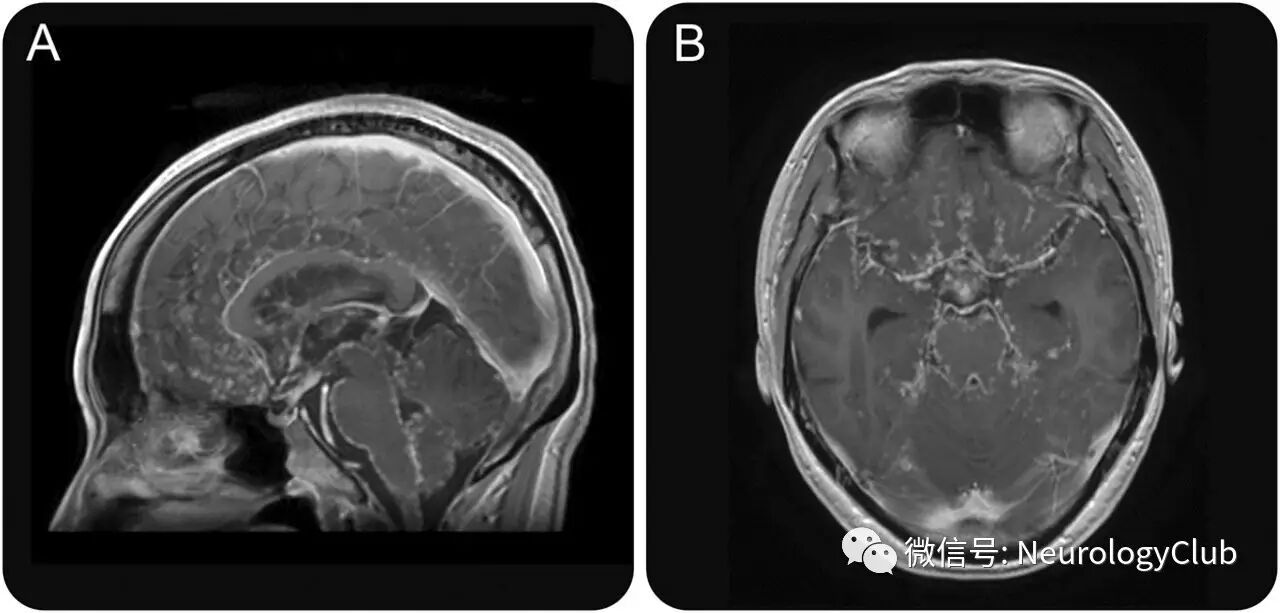

35岁女性,表现为慢性头痛2月。既往有双侧葡萄膜炎。无颈项强直和神经系统功能缺损。脑脊液提示淋巴细胞数增多,蛋白升高,糖减少(23mg/dL)。抗酸杆菌培养阴性。胸部X片提示双侧肺门淋巴结肿大。支气管肺泡灌洗样本中CD4/CD8比例升高。血管紧张素转化酶14.5IU/L。头颅MRI提示主要沿着脑干表面的结节样软脑膜强化,形似“珍珠串”(图)。

(图:矢状位[A]和横断面[B]T1增强MRI可见软脑膜串珠样强化)